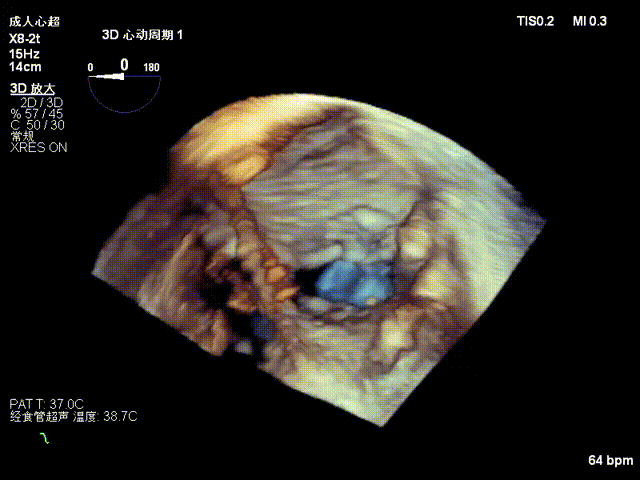

2.Annuloplasty Effect: Annular morphology remodeled, central gap significantly reduced.

Preoperative 3D

Postoperative 3D